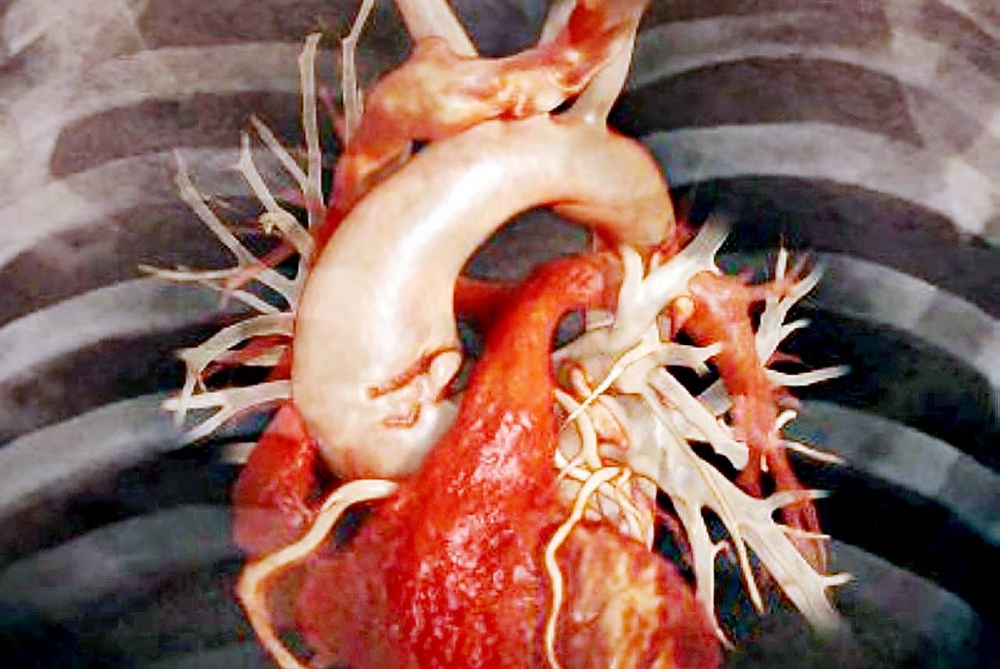

طوّر الباحثون من جامعة تينيسي الأمريكية، جهازاً إشعاعياً جديداً لإنشاء صور عالية الجودة للداء النشواني القلبي، وهي حالة مشابهة لمرض الزهايمر، ولكنها تؤثر في القلب.

ويعد هذا الكاشف الإشعاعي، وفقاً لبحث تم تقديمه في الاجتماع السنوي لجمعية الطب النووي والتصوير الجزيئي 2024، الأول من نوعه المصمم خصيصاً للكشف المبكر عن الداء النشواني القلبي وعلاجه.

ويعد هذا الكاشف الإشعاعي، وفقاً لبحث تم تقديمه في الاجتماع السنوي لجمعية الطب النووي والتصوير الجزيئي 2024، الأول من نوعه المصمم خصيصاً للكشف المبكر عن الداء النشواني القلبي وعلاجه.